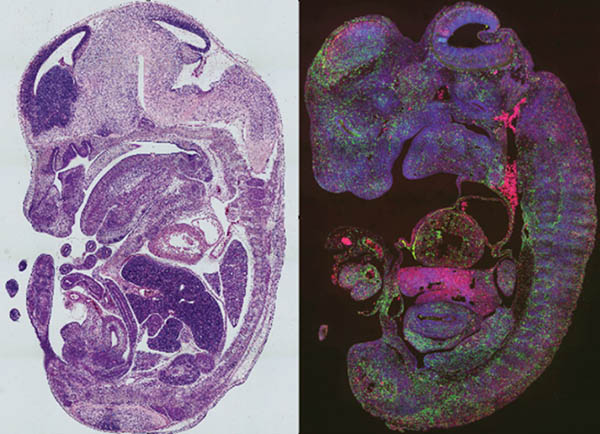

The Heart Development and Regeneration Lab aims to understand the fundamental mechanisms of cardiac cell proliferation and differentiation and how signaling communications instruct these processes:

The lab takes advantage of multiple cutting-edge technologies, including single cell RNA sequencing, ribosome profiling, ChIP-sequencing, CROP-Seq, ATAC-Seq, special transcriptomics, proteomics, CRISPR-Cas9 and confocal imaging, and generates and uses genetic mouse models and human induced pluripotent cells to tackle these and other important questions in the field.

Congenital heart disease (CHD) is the most common birth defect, affecting nearly 1% of live births. By expanding knowledge of the pathogenesis of CHD, the lab team aims to improve CHD treatment and prevention and adult heart repair and regeneration.

A key process in heart development is ventricular trabeculation and compaction. The failure of this process can result in left ventricular noncompaction cardiomyopathy (LVNC), the third most common form of cardiomyopathy. The etiology of LVNC is still poorly understood, warranting further investigation.

During early heart development, the derivation and commitment of each cardiac lineage is crucial for later cardiac morphogenesis. However, in-depth understandings of lineage specification are still lacking.

Our lab is interested in learning how cardiac lineages are defined at epigenetic level. For instance, how chromatin accessibility may sculpture diversified cardiac lineages including subtypes of cardiomyocyte lineages.